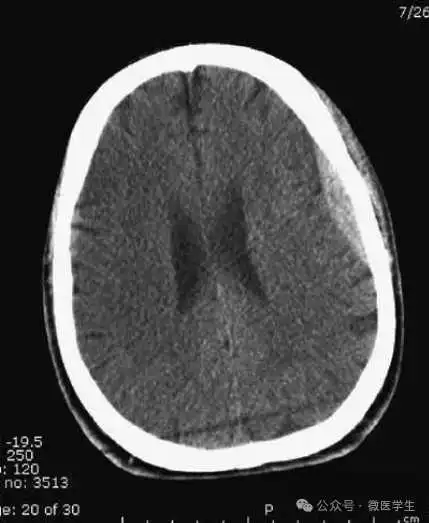

左侧大脑中动脉供血区脑梗死(亚急性期):

低密度,轻度水肿

缺血性脑卒中发作2-4天时,占位效应最明显。